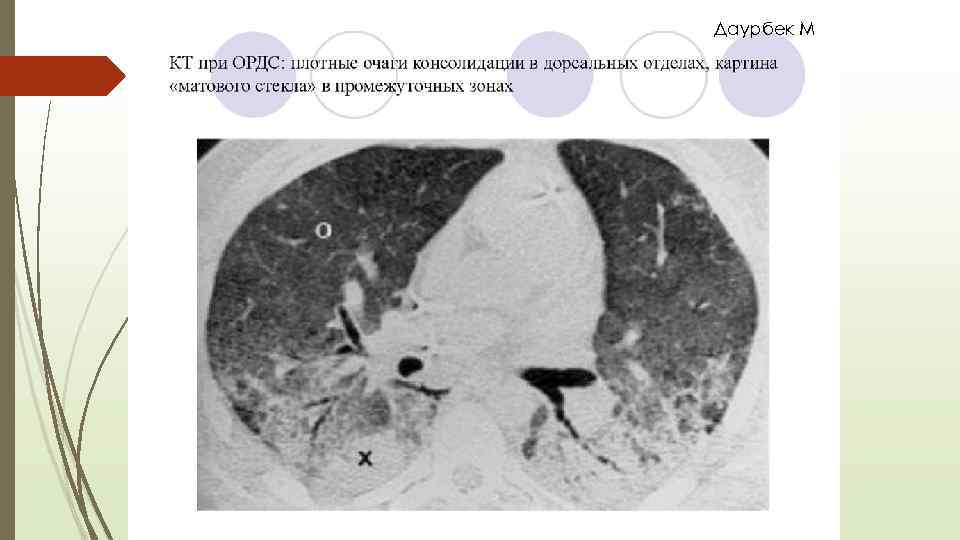

Даурбек М 1990 жылы Фишер мен Фоекс РДС диагностикалық критерийіне келесілерді ұсынды: Интерстициальды өкпе ісінуі ( матовое стекло, снежная буря)

Даурбек М